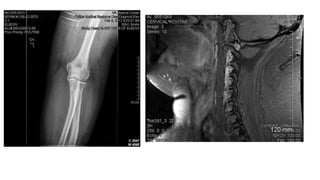

A partir dos anos 1960, começaram

a aparecer pessoas com estranhas

marcas no corpo: cicatrizes,

pequenas cavidades, cortes por laser

em série.

São o resultado de cirurgias,

desinfecção, retirada de fluidos,

inserção de microchips...

Marcas nos abduzidos Apartir dos anos 1960, começaram a aparecer pessoas com estranhas marcas no corpo: cicatrizes, pequenas cavidades, cortes por laser em série. Tornozelo, pulso, costas, quadris, seios etc. São o resultado de cirurgias, desinfecção, retirada de fluidos, inserção de microchips...

mais de 50milhões de IMPLANTES ALIENÍGENAS em todo o mundo Implantes são microchips que servem para: - Rastreamento/monitoramento - Controle mental - Aperfeiçoamento genético/energético

Este tipo deimplante é encontrado em inúmeros abduzidos